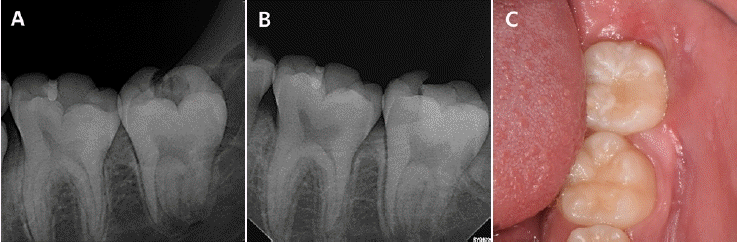

다발성 치아 맹출 장애로 본원에서 치료 중이던 13세 남아에서, 상악 좌측 견치와 제1소구치의 견인을 위한 외과적 노출술 시행 중 두 치아의 치관 교두정 부위에서 부분적 결손이 관찰되었다(Fig. 3C). 환아는 특이한 의학적 병력이 없었으며, 과거 촬영된 방사선 사진에서 해당 치아의 치관부에 방사선 투과상이 관찰되어 PEIR으로 진단하였다(Figs. 3A and B).외과적 노출 시 병소의 입구를 조심스럽게 제거한 결과, 상악 좌측 견치와 제1소구치 모두에서 치수와 개통된 광범위한 흡수성 병소가 확인되었다. 이에 두 치아에 직접 치수 복조술을 시행하였으며, calcium silicate 계열 복조재인 Biodentine (Septodont Corp., Paris, France)을 적용한 뒤, GI (Riva, SDI, Victoria, Australia)를 충전하였다(Figs. 4A and B).이후 11개월 경과 시 견인술을 통해 치아의 맹출이 이루어졌고, 임상 및 방사선학적 검사에서 이상 소견이 관찰되지 않았다(Figs. 4C and D). GI 수복물을 제거하고 접착제(Scotchbond Universal Adhesive, Solventum, St. Paul, MN, USA)를 도포한 후 복합레진(Filtek Z250 Universal Restorative A2, Solventum, St. Paul, MN, USA)을 이용한 영구 수복을 시행하였다. 환아는 이후 장기간 본원에 내원하여 정기적인 경과 관찰을 받았으며, 9년 간의 추적관찰 기간 동안 별다른 증상은 발생하지 않았으며 치관부에 잔존하는 치관부 방사선 투과상은 변화 없이 유지되었다. (Figs. 5A-C). 9년 후 임상검사 상 치관부의 변색 및 방사선 사진 상 삼차 상아질 형성이 관찰되었으며 추가적인 치료는 시행하지 않았다(Figs. 5D and E).- 증례 3

Figure 4.

Intraoral photographs and intraoral radiograph during treatment. A. Following Biodentine placement. B. Following GI application. C. After approximately 3 months of orthodontic traction, the tooth erupted, and the GI restoration remained intact. D. Periapical radiograph after eruption.

Figure 5.

Radiographs and Intraoral photographs during follow-up. A. 3-year follow-up. B. 6-year follow-up. C. 9-year follow-up. D. Periapical radiograph at 9-year follow-up. E. Intraoral clinical photograph at 9-year follow-up.